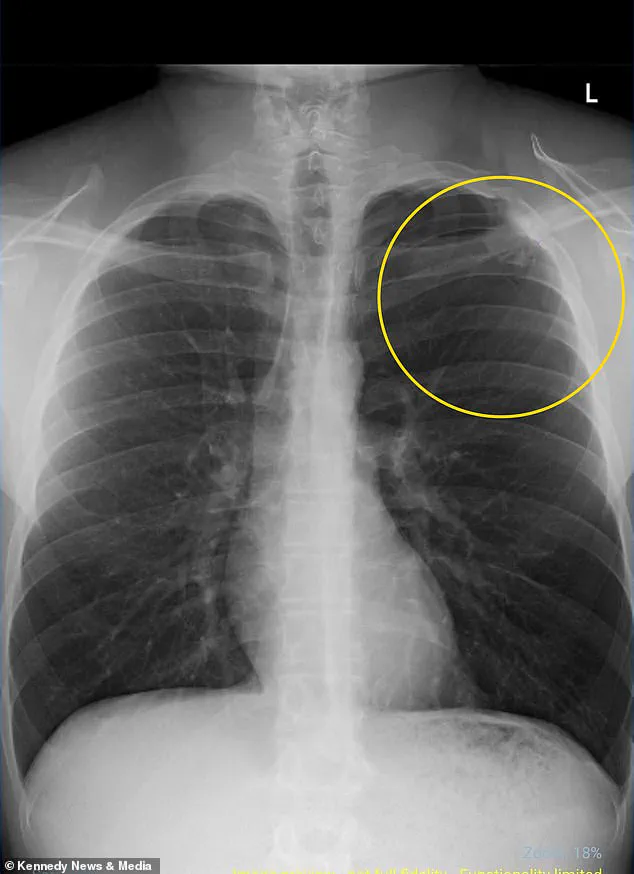

Rushed to the hospital, doctors diagnosed him with a partially collapsed lung, a condition known as a pneumothorax, which occurs when air leaks into the chest cavity, compressing the lung and impairing its function.

The diagnosis was stark: the collapse was 100% linked to vaping, according to medical professionals, and the damage could potentially recur even if he never vaped again.

While the collapse in Williams’ case was minor—only 10% of his left lung was affected—doctors warned that the long-term damage to his lung tissue could increase his risk of future complications, including infections and recurring collapses.